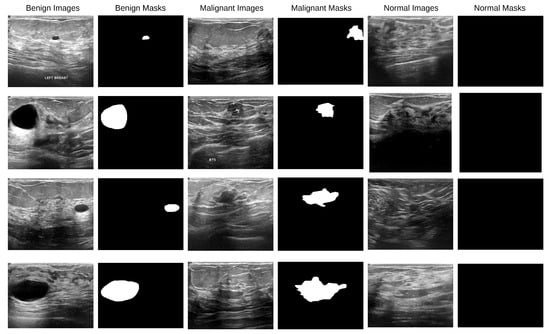

A typical combination of photos showing benign and malignant skin lesions can be found in the second dataset [38]. With about 900 photos in the training set and about 350 in the test set, the dataset was divided into training and test sets at random. The JPEG file format is used for every single picture. The initial photo was used as training data for lesion segmentation, together with the expert manual tracing of the lesion boundaries in the form of a binary mask, where pixels with values of 255 are regarded as being inside the lesion area and pixels with values of 0 as being outside. In Figure 3, a data sample is displayed.

Figure 3. ISIC dataset images along with their corresponding binary ground-truth masks.